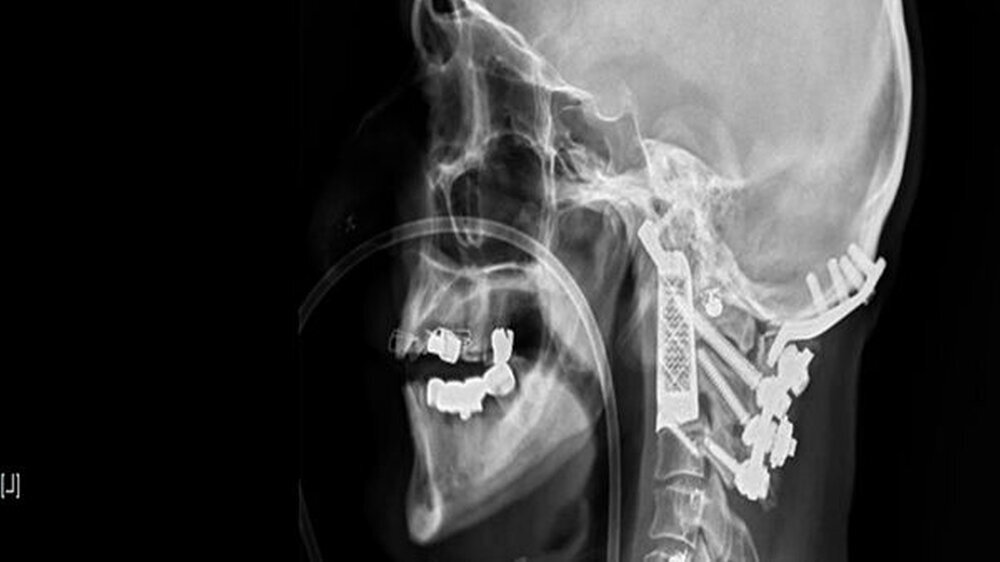

Erstmals Halswirbel aus dem 3-D-Drucker implantiert

Das Team um den Neurochirurgen Dr. Ralph Mobbs implantierte dem Australier Drage Josevski einen Halswirbel aus einem 3-D-Drucker. Josevski litt an dem sehr seltenen Wirbelsäulenkrebs und konnte mithilfe des medizinischen 3-D-Drucks gerettet werden.

Mobbs und seine Kollegen entwarfen die Prothese mit einer speziellen Software und berechneten die Lücke, die der entfernte Tumor hinterlassen würde. Am Ende passte der Halswirbel aus dem 3-D-Drucker tadellos.

Zweieinhalb Monate nach dem Eingriff im Dezember besuchte Mobbs seinen Ausnahmepatienten Zuhause: Josevski hat derzeit noch Probleme beim Sprechen und Essen. Das sei aber dem Procedere der Operation geschuldet, sagt Mobbs. Bei dem OP-Marathon gelangten die Ärzte durch den Mund ihres Patienten an die betroffene Stelle. Daher wurde der Josevskis Rachen 15 Stunden lang durch Luftströmung und OP-Instrumente gereizt. In sechs Monaten seien die Beschwerden verschwunden, versprach der Neurochirurg. Josevski könne dann mit dem 3-D-Drucker-Halswirbel wieder ein ganz normales Leben führen.